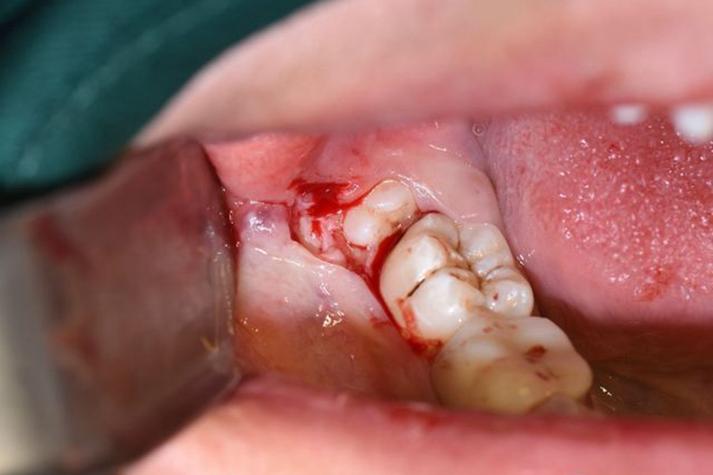

随着智齿继续萌出,如果空间不足,智齿可能会倾斜生长,部分牙龈覆盖在牙冠表面,形成一个盲袋,这个盲袋容易食物残渣和细菌积聚,日常刷牙很难彻底清洁,久而久之,细菌大量繁殖,引发冠周炎,这是长智齿最常见的问题之一,冠周炎的症状会明显加重,牙龈出现剧烈疼痛,疼痛可放射至头部、颈部和肩部,导致患者张口受限,甚至无法正常进食,说话和吞咽也会受到影响,此时牙龈红肿更加明显,表面可能出现脓液,按压时有脓液溢出,同时伴有口腔异味,即使认真刷牙也无法消除,严重时还可能出现发烧、头痛、全身乏力等全身症状,颌下淋巴结也可能肿大并伴有压痛。

除了冠周炎,长智齿还可能引发其他口腔问题,如果智齿萌出方向异常,如水平阻生、近中阻生等,可能会压迫邻牙,导致邻牙龋坏或牙根吸收,患者可能感到邻牙疼痛或松动,如果智齿完全埋在颌骨内,形成阻生齿,随着时间推移,可能会在颌骨内形成囊肿或肿瘤,破坏颌骨组织,这种情况早期可能没有明显症状,但通过口腔X光检查可以发现,当囊肿较大时,可能会导致面部膨隆、牙齿移位等症状,长智齿还可能引发颞下颌关节紊乱,患者感到张口时关节弹响、疼痛,甚至出现张口受限。